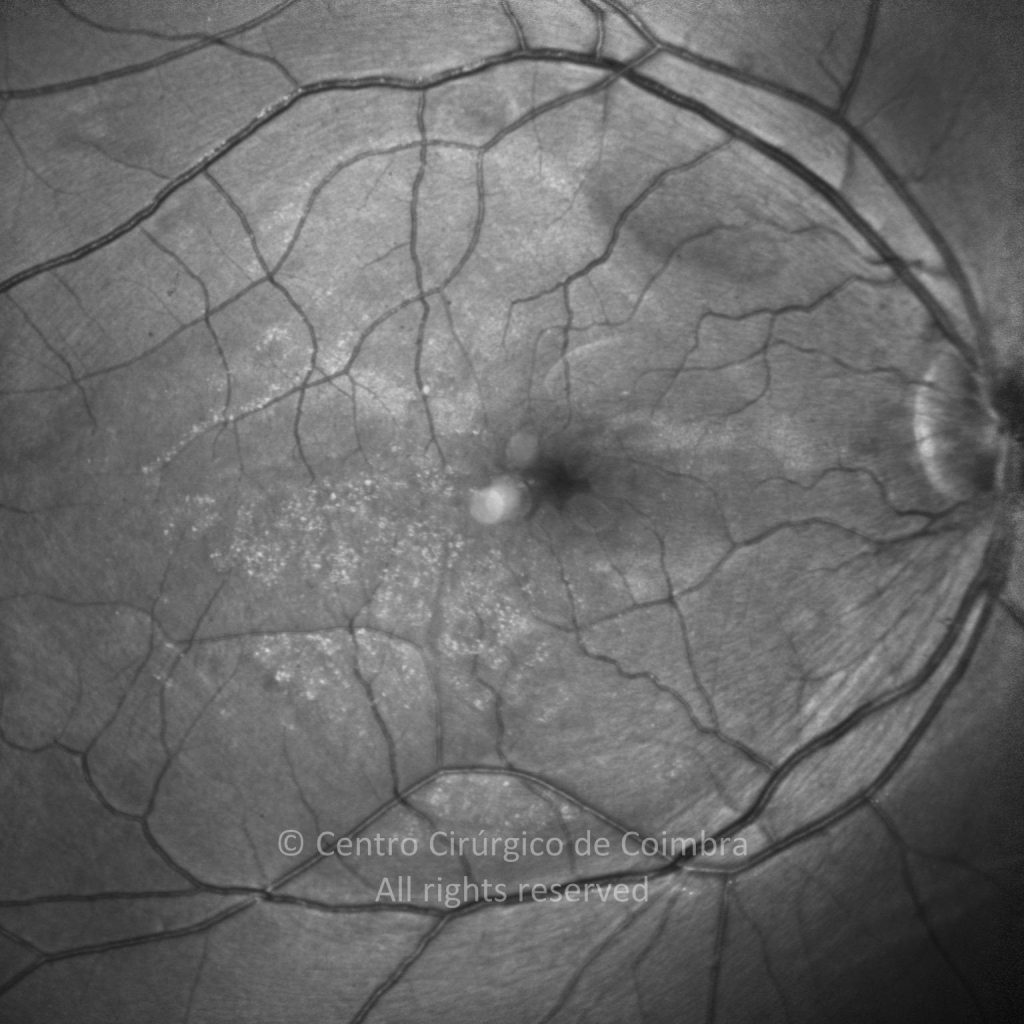

Paciente de 37 años con traumatismo contundente y ruptura del globo ocular. Presenta ruptura esclero-uveal, hifema, hemovítreo, desgarro periférico y temporal de la retina, hemorragias subretinianas y múltiples desprendimientos serosos.

MAVC: 20/25 OD, nueve años después de las cirugías (sutura escleral de la desinserción del músculo recto externo, vitrectomía posterior y fotocoagulación láser en el borde del desgarro retiniano, desprendimiento de retina inferior con proliferación vitreorretiniana y líquido subretiniano con algo de sangre; peeling de la membrana epirretiniana y maculorrexis de la MLI).